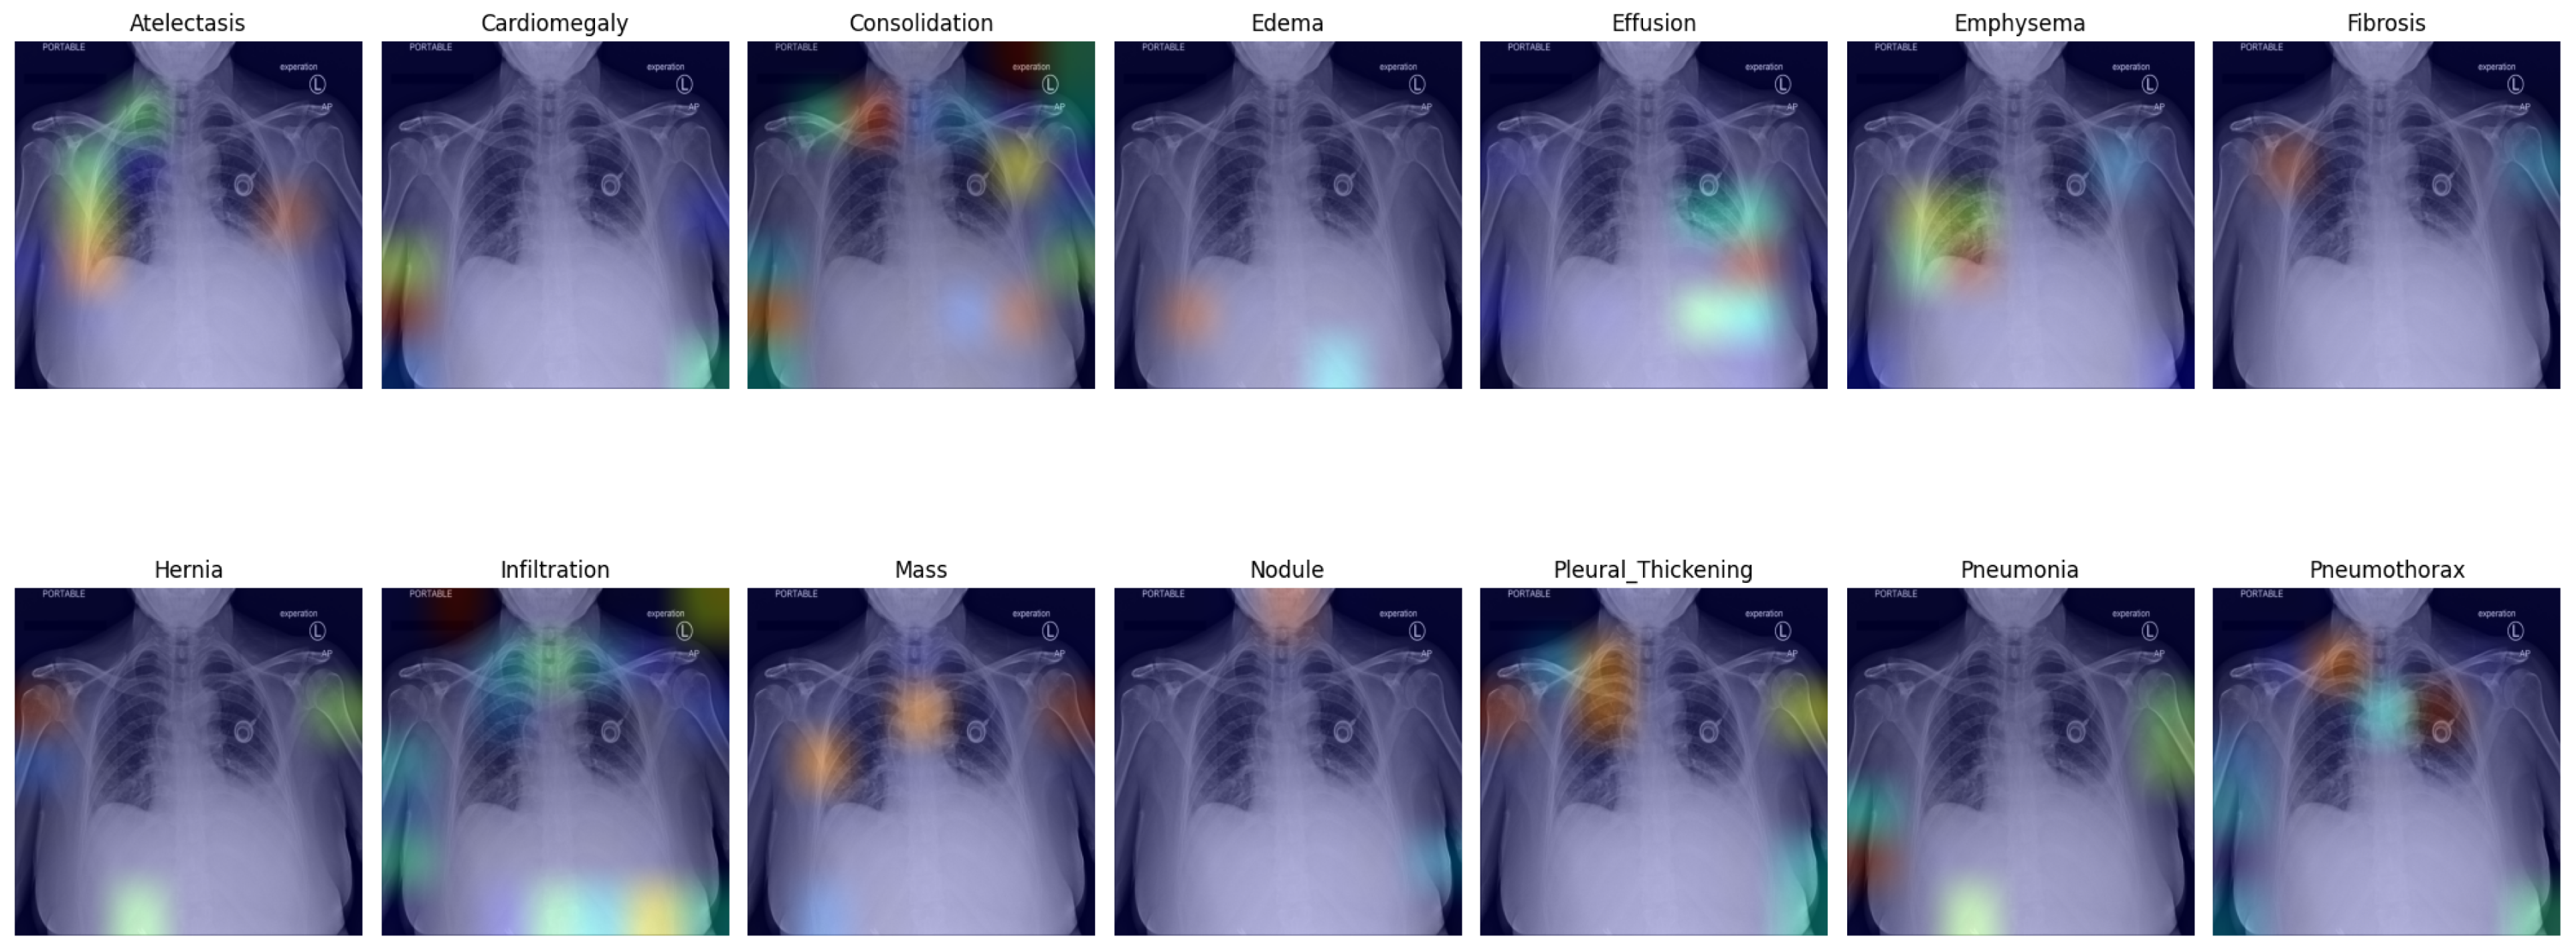

Pulmonary infiltrate is a non-specific term for any accumulated abnormal substance in the lungs; further differentiation is needed for pneumonia, atelectasis, hemorrhage, edema, fibrosis, etc. In Figure 2, we show selected X-rays for preview. Air spaces may be filled with fluid, pus, or cells, causing increased whiteness due to increased attenuation of the X-rays, called consolidation. The accumulation of fluid in the lungs in pulmonary edema has multiple signs, including pleural effusion, air space opacification in a batwing distribution, and enlargement of the heart (cardiomegaly).

The expansion of the lungs may be incomplete for various reasons. Atelectasis is the incomplete expansion of some regions of the pulmonary tissue, while pneumothorax (PTX) is complete lung collapse due to air entering the plural places. On plain radiographs, PTX can be identified by the visible visceral pleural edge, which appears as a thin sharp white line with no lung markings peripheral to this line, and we can detect nodules and masses that are abnormal growths in the lung, which may represent tumors. Malignant conditions may have other signs, such as thickening of the pleura. Inflammatory conditions, e.g., pneumonia, have distinctive signs as well, including patchy or large areas of consolidation.

Figure 2. Chest X-ray images with findings: (a) hernia; (b) atelectasis, cardiomegaly, edema, effusion, and infiltration; (c) cardiomegaly, consolidation, effusion emphysema, infiltration, pleural thickening, and pneumothorax; (d) no findings.